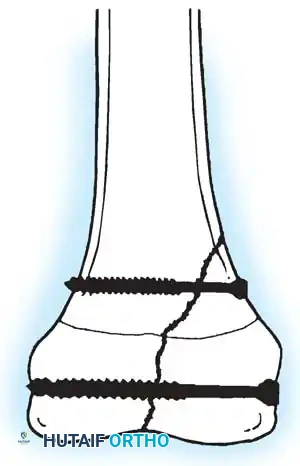

Fig. 33-146: Subtrochanteric fracture stability. (A) If the proximal spike of bone is posterior, the fracture is often stable against the distal fragment. (B) Conversely, if the proximal spike is anterior, the fracture is highly unstable, and 90-90 traction or operative fixation is necessary to counteract the flexion force of the iliopsoas.